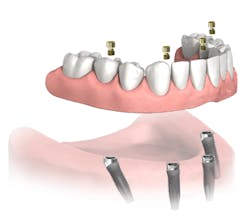

MY COLLEAGUES FREQUENTLY ASK ME what my hygiene follow-up protocol is for full-arch All-on-4fixed bridges (Nobel Biocare; figure 1). There seems to be a wide spectrum as to how clinicians treat patients after their final All-on-4 bridge is delivered, and I am sure that many options exist to adequately manage these patients in the dental hygiene department.

Figure 1: Fixed full-arch bridge